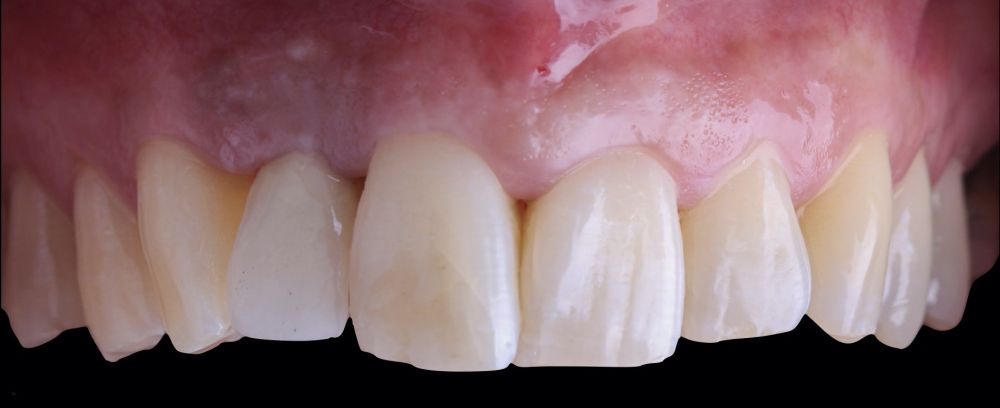

* Phase III: three months after implant placement, the soft tissue condition was favourable (Figures 5 and 6). A digital impression was obtained using an intraoral scanner for the fabrication of a screwretained

polymethyl methacrylate (PMMA) provisional restoration. Regarding the definitive

implant crown, a cement-screw-retained

restoration was fabricated with a titanium nitride interface, adapting the design to the emergence profile already consolidated with the provisional prosthesis. The crown was produced by CAD-CAM in zirconia with full reduction and feldspathic ceramic veneering for zirconia (Figure 7).